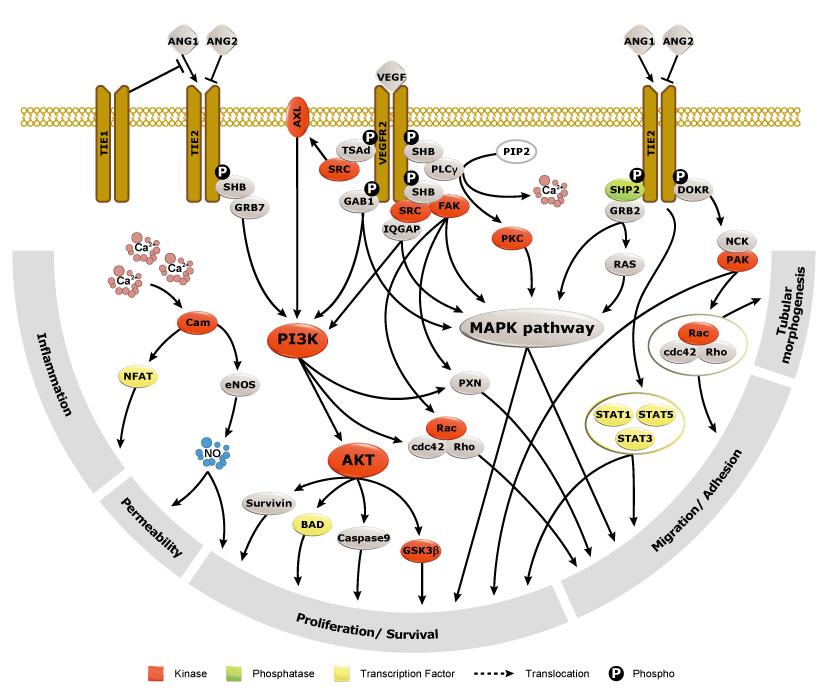

Angiogenesis entails the generation of new blood vessels from pre-existing vasculature. It is an intricate process tightly regulated by input from pro- and anti-angiogenic factors. In the normal adult, the balance between these inducers and inhibitors maintains a quiescent state that nevertheless is capable of rapid changes in response to micro-environmental disruptions secondary to wounds, hypoxia, or inflammation. Perturbations of this balance in various chronic pathological conditions and tumors can lead to inappropriate angiogenesis or neovascularization. The mechanistic features underlying angiogenesis are complex, but the clinical importance of being able to modulate this process means that this will remain a compelling and dynamic field of research.